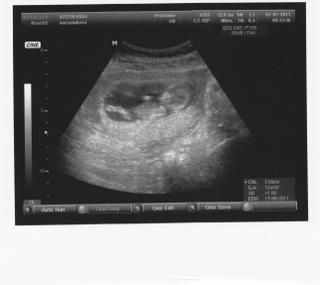

@charlize uaaaaau budes laktacna? to je uzasne. danko je sikulik ;-) najkrajsi na svete. My sa mame fyzicky dobre akurat moj gyndos zataz na moju psychiku po vcerajsej poradni tak na sebe teraz pracujem aby som sa naspat vyladila. Zajtra idem za PA do spisskej, velmi sa tesim je to moj tehotensky anjel. budeme mat dlhuuu poradnu preberieme si tehotenstvo, predstavy o porode (domacu aj nemocnicnu cast) co potrebujem a ocakavam od nej aj od muza, komplet ma opat prezrie aj maleho. velmi sa tesim. maal sm si pripravit porodne prianie aby si zafixovala co je pre mna dolezite a vedela mi to pomoct zabezpecit. Natrafila som na tolko uzasnych ludi pocas tehotenstva ze ma to uistuje ze som si zvolila spravnu cestu. Velmi mi pomaha aj neonatologicka- strazny anjel, ktora mi pripravuje v porodnici cesticku, masiruje porodnikov aby mi vysli v ustrety. Vela veci spolu konzultujeme, piseme si maily az mam pocit ze sa z nas stali kamaratky. Pediatricku som nasla tiez uzasnu, je antiocko a prirodna tak som uplne nadsena. Dnes idem na masaz lebo mi zacali po dlhsom sedeni v praci trochu opuchat nohy tak dula fyzioterapeutka sa mi ponukla ze mi povzbudi trochu lymfo system nech ulavime oblickam. malinky je zlatucky vcer amse boli na usg v 30tt tak v jednej chvili na cely monitor len jeho megavajca :-D tak muz bol rad ze s nami nevypiekol a nema nakoniec predsa len šušku. :-) super ze mas danka skor, aspon mi potom podavas rady o tych prikrmoch, presne tak by som to chcela robit ze tie bio kasicky s vysokou nutricnou hodnotou, ovocie zeleninu, tak si oskusat dajake recepty a potom posunies. ak by sa mi podarilo byt do porodu v BA mohli by sme sa aj konecne stretnut. :-) velmi rada by som vas videla

@charlize @danka.chomka bea hej platim si dnp samozrejme, teraz to nechat by bola hlupost... ale dobre s tym stresovali raz taky navrh, raz taky... nakoniec to ale aspon pre mna este dobre dopadlo :-D uz len aby sme boli vsetci traja zdravi a vsetko bude v poriadku... v pondelok ideme na usg v 12tt, potom budem o drobcovi vediet viac x-) aj na socialku chcem ist este radsej osobne, nech to mam aj od nich a nie len z netu potvrdene... inac sa citim v pohode, ziadne nevolnosti... akurat mi zacinaju byt tesne nohavice na pase =-) buduci vikend ideme otcovi na 50tku, neviem co na seba navleciem, bude treba ist na nakupy :-S cela rodina si ma bude obzerat uz to vidim... a pomaly ale isto mi pekne zacina rast brusko, podprdy uz som si musela kupit tiez vacsie na co sa ale nestazujem :-D a s rastom uz planujeme co kde kupime, zozenieme... babkam sme oznamili ze budu strikovat :-D strasne rychlo to ide poviem vam... este len teraz som si nasla II a buduci tyzden zaciname druhy trimester x-) x-) bea dankove prikrmy som videla na konovi, aj ako si pochutnaval ;-) velmi je sikovny, len tak dalej... moj synovec zacal sam chodit az ked mal 18 mesiacov, a o 3 tyzdne ma 2 roky a este stale nerozprava :-| ale narodil sa predcasne, mal vyvod, aj nejake operacie tak to pripisuju tomu... a danka vam to tiez rychlo bezi, co nevidiet budete traja x-) a co bolo s gyndosom ze ta tak rozhadzal? mas nejakeho neprijemneho ci len bol velmi mudry? pekny vikend vam zelam babuse ;-) uz sa neviem dockat pondelku kedy ho zas uvidim x-) x-)

@danka.chomka @charlize no uz sme po kontrole, vsetko je v poriadku, primerane k 12tt x-) podla pm sme 12+1tt, podla velkosti 12+3 tt. krasne bolo vsetko vidno na sone, poukazovala mi kde co ma... nechcel sa jej dobre ukazat na meranie tak som musela kaslat aby sme ho "zobudili" :-D potom sa rozhybal. a pytala som sa jej na femibion, ci mam po 12tt prejst na 400 ako je napisane v navode, tak vravela ze mam prestat brat taketo vitaminy, pretoze podporuju velkost babatka a ja som mala zena, takze ak bude velke dieta bude problem pri porode a pravdepodobne by trebalo cisarak takze netreba "umelo" podporovat velkost. mam jest viac zeleniny a ovocia a drobec si vezme co potrebuje, co vy na to vyjadroval sa k vitaminom nejako vas lekar? kyselinku som brala 3 mesiace pred pocatim a odkedy viem o tehu tak som presla na femibion 800. dani ked sa ti chce doktor cez taketo "zastrasovanie" pomstit tak je to od neho dost neprofesionalne, stresovat zenu v takom stadiu tehu bez objektivnych dokazov :-S ja uz sa neviem dockat kedy zacneme tiez nakupovat vybavicku, zatial sme kupili nejake body co mali v tescu za super ceny, taky rozkosny kabatik na zimu univerzalny aj na dievca aj na chalana x-) a mam taku krasnu plysovu hracku co hra uspavanky... s ostatnym pockame na neskor zatial, pripadne keby boli velmi vyhodne ceny tak kupime skor. na tie plienky asi pockam ako pisala bea na plienkovy tyzden ;-)